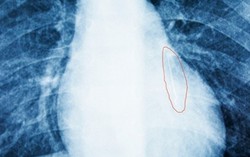

Kim khâu chạy từ lưng sang ngực đâm xuyên phổi bé 3 tuổi

Phòng & chữa bệnh 16:04 24/10/2017Khi bé bị ngã, chiếc kim đâm vào lưng nhưng không ai biết. Sau 2 năm, chiếc kim khâu đã di chuyển, đi qua lồng ngực, xuyên vào phổi. Gần đây, khi đi khám, bác sĩ mới phát hiện ra chiếc kim nằm trong lồng ngực bé đã bị rỉ sét.

Kim khâu dài 2,5cm trong phổi bệnh nhi

Phòng & chữa bệnh 17:32 01/06/2016Thấy bé khó thở, nuốt khó, gia đình đưa đến BV để thăm khám. Các bác sĩ đã phát hiện có dị vật hình chiếc kim khâu nhọn nằm ở vị trí 1/3 dưới phổi trái nên tiến hành nội soi.